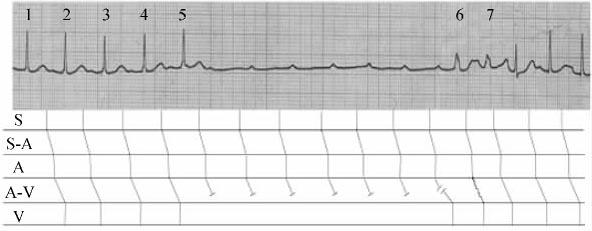

高度房室阻滞时,在交界性逸搏、室性逸搏或人工心室起搏后,出现连续的窦性心室夺获,系由隐匿性逆向传导引起重复的超常期前向传导所致,或称为韦金斯基现象(图2207)。

图2-20-7 高度房室传导阻滞的韦金斯基现象

第1、2、3、4、5 QRS波形态正常,与其前之P波关系固定,P-R为0.24s,属窦性心动,Ⅰ度房室传导阻滞。其后出现暂时性高度房室传导阻滞遂使相继出现7个窦性P波未能下传。图中第6号畸形、增宽的QRS波(0.12s)为室性逸搏。然而由于该室性逸搏所引起的韦金斯基易化作用,遂使其后的一个窦性冲动能下传至心室,因室性逸搏前的R-R间距长达4.8s,故该窦性冲动下传至心室呈差异性改变,第7号畸形、增宽的QRS波。继此后的连续3次窦性冲动,所以能下传至心室则系韦金斯基效应所致